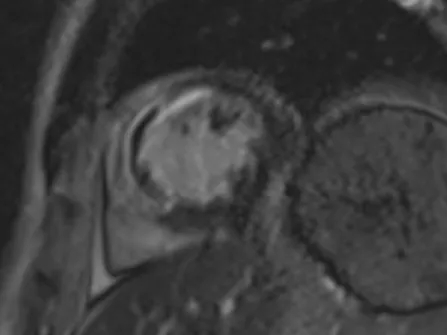

PCI术后即刻应用基于压力导丝的冠脉功能学全面评估解决方案(IMR/FFR等)进行全面评估,测得LAD IMR 46(+),FFR 0.87,提示存在CMD。心脏磁共振结果也提示存在微血管阻塞。